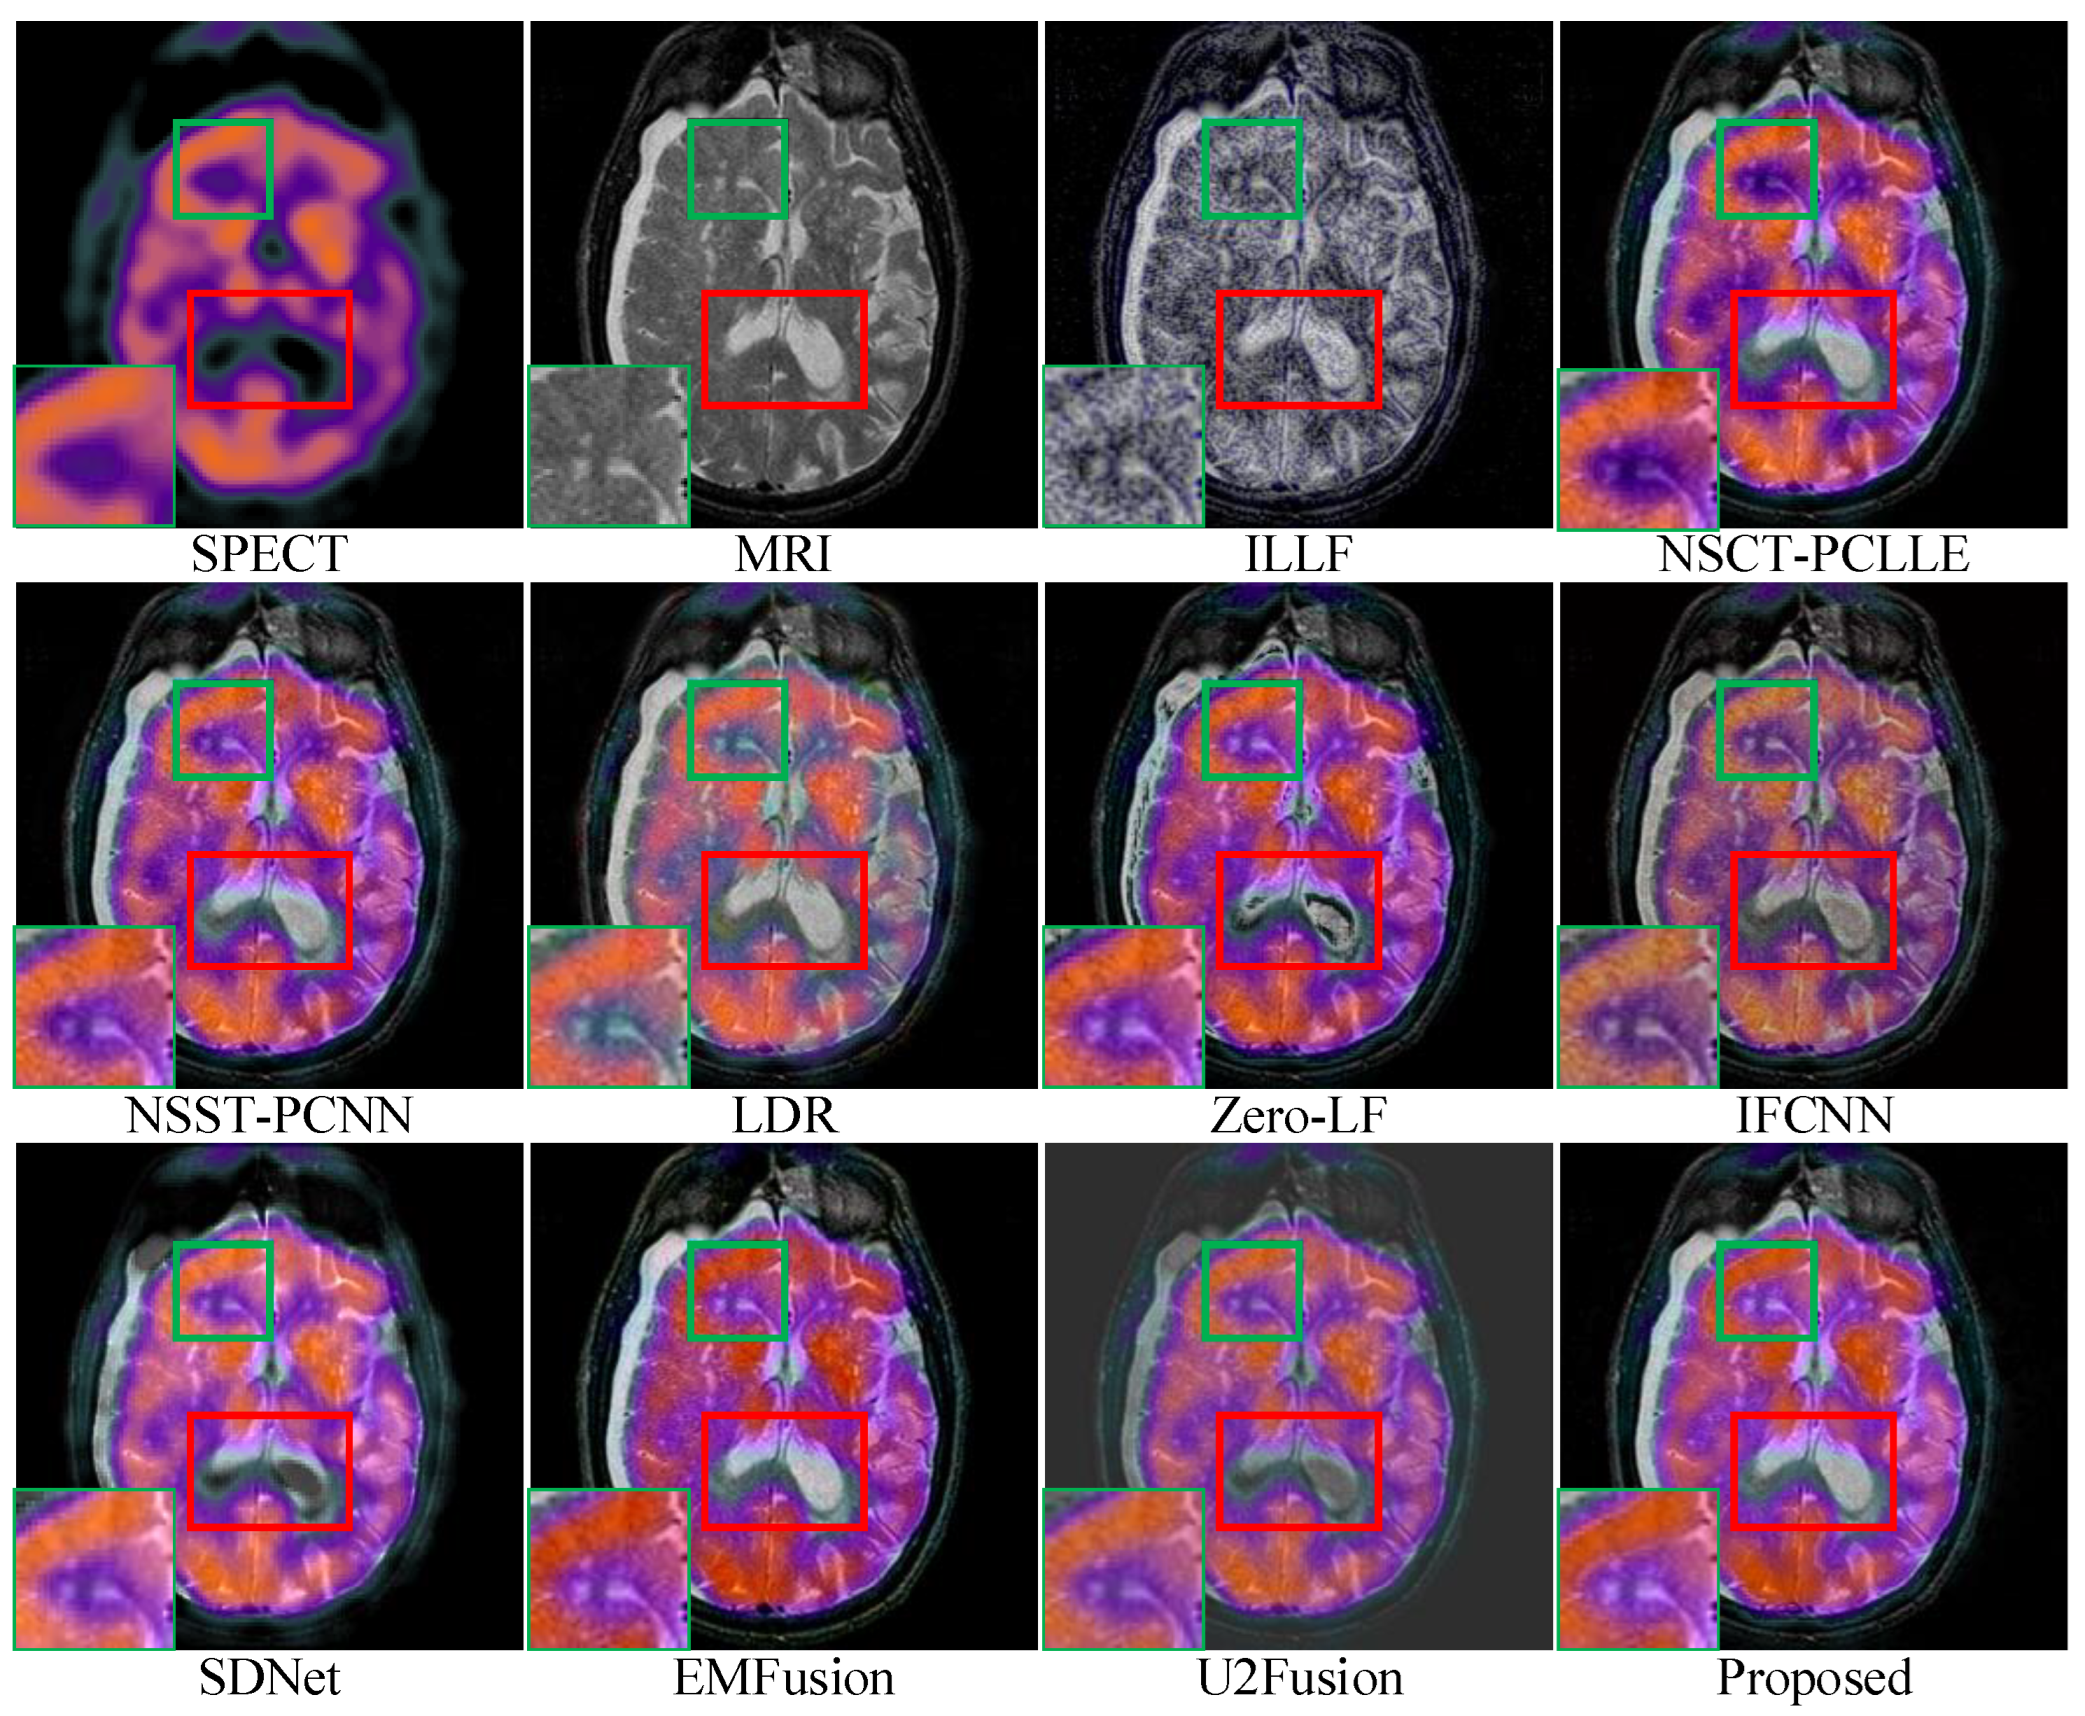

For conciseness, we have only shown the results of three sets of images in the subjective evaluation. Figure 5, Figure 6 and Figure 7 show the fusion results of different types of medical images obtained by different image fusion algorithms.

Figure 7.

Comparison of performances of various methods on the single-photon emission computed tomography (SPECT)-MRI images. For a clear comparison, we select two same regions (i.e., the green and red boxes) in each image, and the green boxes are zoomed in the bottom left corner.

In Figure 7, under ILLF, LDR, IFCNN, and EMFusion, there are deviations in color in the source SPECT image. Regarding the source image, the ILLF results show grayscale information, the LDR and IFCNN results show lighter colors, and the EMFusion results show color enhancement. NSCT-PCLLE, NSST-PCNN, Zero-LF, SDNet, and U2Fusion did not completely capture the luminance information of the MRI images, and this is represented by a small black shading in the marked red area. The fusion results of NSCT-PCLLE, NSST-PCNN, Zero-LF, SDNet, and U2Fusion show black blocks. As shown by the green enlarged area in the lower left corner of the images, ILLF, NSST-PCLLE, LDR, IFCNN, SDNet, and U2Fusion were not completely capable of retaining the details in the source image, while our method was able to retain them well. Figure 7 shows that the images fused under our proposed method are more informative, clearer, and have a higher contrast than those under the existing methods.